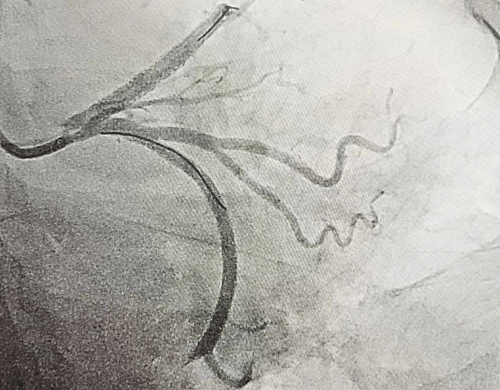

51歲的郭女士,因反復(fù)胸痛3天,加重2小時(shí)入院,入院后胸痛癥狀反復(fù)發(fā)作,檢查心電圖提示前壁導(dǎo)聯(lián)ST段明顯壓低,在此危急時(shí)刻心九科值班醫(yī)生陶醫(yī)生立即啟動(dòng)導(dǎo)管室,心九科介入團(tuán)隊(duì)行冠脈造影提示患者前降支近段99%狹窄,患者病情危在旦夕,遂立即行支架植入術(shù)解除冠脈狹窄,患者生命得以及時(shí)救治。

冠脈手術(shù)前